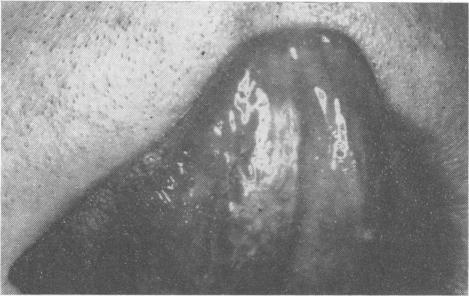

Leukoplakia and oral cancer.

Proc R Soc Med. 1969 Jun;62(6):610-5. doi: 10.1177/003591576906200637.